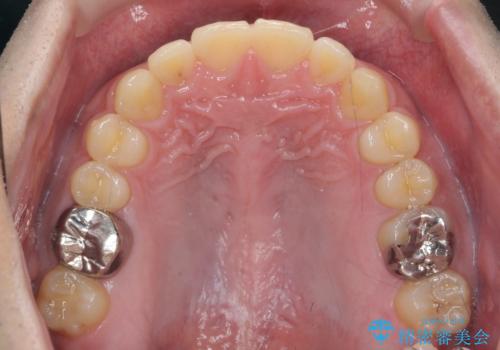

- 前歯の噛み合わせが反対になっていること、前歯の見た目の改善を希望され来院されました。

詳細な矯正検査の結果、顎の歪みが見られたため大きく歯を動かす治療ではなく前歯を主に並べることで前歯の前後関係を改善していきます。

前歯を主に動かす部分矯正であることからマウスピース矯正インビザラインによる治療を計画します。